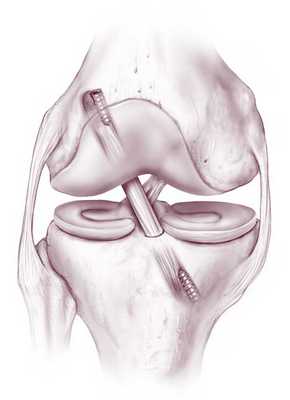

Передняя крестообразная связка отвечает за динамическую устойчивость коленного сустава, фиксируя голень от нефизиологического смещения кпереди и поддерживая наружный мыщелок большой берцовой кости. Более 1/2 стабильности коленного отдела обеспечивается благодаря ПКС. Именно поэтому данную структуру специалисты называют первым стабилизатором колена, без нее сустав нормально работать не сможет. Располагается она в самом центре костного соединения, перекрещиваясь с задней крестообразной связкой х-образно, что и дало этим двум структурным элементам одноименные названия. Мы же будем говорить сейчас конкретно о ПКС и посттравматической реконструктивно-пластической ее коррекции.

Операция на ПКС: виды пластики, принцип выполнения

Любая пластическая процедура на ПКС в настоящий момент выполняется методом малоинвазивной артроскопии. Артроскопический сеанс проходит закрытым способом под спинномозговой анестезией. Операция относится к щадящему типу хирургии высокой точности, поэтому мягким тканям, нервным и сосудистым образованиям не причиняется ущерб. Кроме того, манипуляции проводятся сугубо на пострадавшем участке, а после вмешательства никаких рубцов и шрамов не остается.

Чтобы осуществить реконструкцию поврежденного элемента, достаточно сделать один 5-мм прокол для оптического зонда, в который встроена миниатюрная видеокамера, и 1-2 дополнительных доступа (не более 8 мм в диаметре). Через вспомогательные отверстия хирург микрохирургическими инструментами будет заниматься воссозданием испорченной области. Зрительный контроль обеспечивает артроскоп (эндоскопический зонд), который выводит изображение оперируемой зоны на монитор в 40-60-кратном увеличении. Оперативное вмешательство может быть выполнено несколькими способами, рассмотрим их дальше.